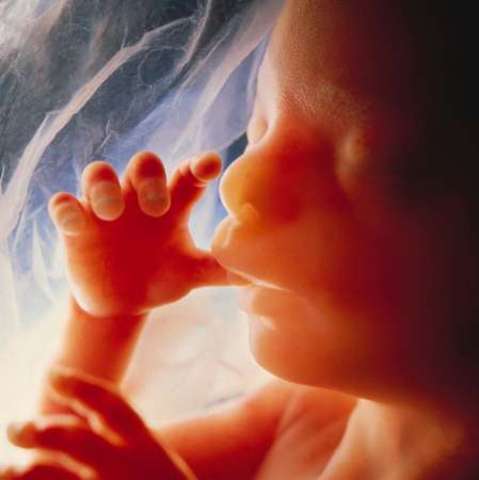

Month Four

Size at the end of this month should be about 6.5 to 7 inches long and about 6 to 7 ounces.

• Reflexes like sucking and swallowing are developing

Reflexes like sucking and swallowing are developing

Skin is covered by a layer of hair.